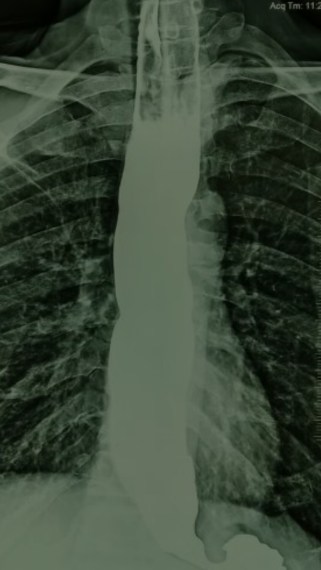

Now,we have every thing. Students read medicine in animated 3D class rooms , physicians get a deluge of body system data & images beamed straight into their ipad . One can perform complex interventions with ease in almost every organ or even replace it , if it doesn’t work .